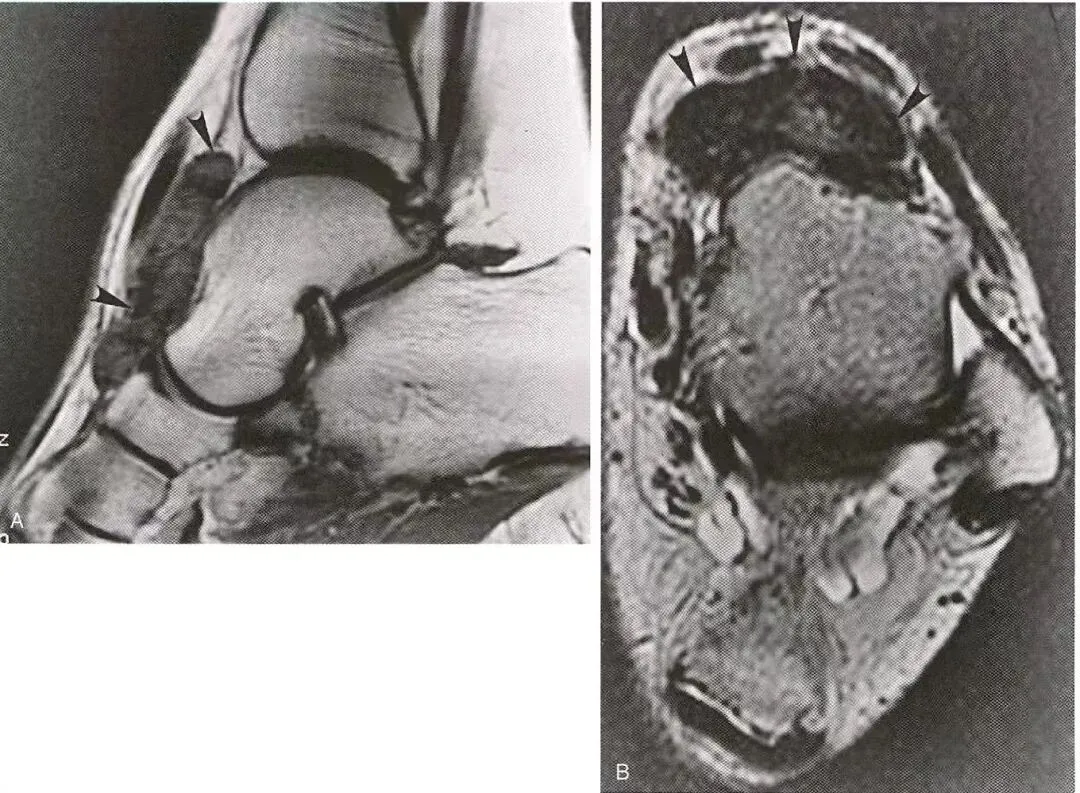

肌腱黄色瘤:  A,跟腱增厚,腱内有异常的条纹状信号,  B,跟腱增厚并前缘膨隆,内有点状低、高信号。